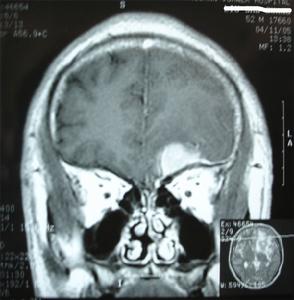

4.MRI MRI對診斷本病是有意義的。MRI可以顯示腫瘤與蝶骨翼和眼眶的關係,骨質破壞情況等。尤其是對內側型的蝶骨嵴腦膜瘤,MRI還可以提供腫瘤與頸內動脈的關係,有時腫瘤將頸內動脈包裹在內,或腫瘤附著在海綿竇上這些情況對手術切除腫瘤均有重要的參考價值。增強後的MRI圖像更清晰。

蝶骨嵴腦膜瘤在T1WI和T2WI上呈低信號或中信號增強明顯和CT相比,MRI對於體積較小的腫瘤顯示較好。顱內惡性腦膜瘤可侵及眶內、顱內,呈多發腫瘤。